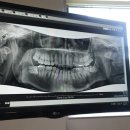

안녕하세요. 뀨뀨입니다. 오늘은 #매복사랑니발치 에 대한 후기를 남기려고 합니다. 7월 23일 왼쪽 #매복사랑니 를 발치하고 8월 13일 오른쪽 매복 사랑니를...꿀팁이 될 것 같습니다.​ ​ 분당제생병원별관 경기도 성남시 분당구 황새울로341번길 23 그래서 방문한 곳이 #분당제생병원 입니다. 분당제생병원의 #치과진료...

뀨뀨의 일상(2021-08-18 21:38:00)

• 황새울로341번길 | 매복사랑니발치 후기1 (분당제생병원 별관)

분당구 황새울로341번길 23 저장 관심 장소를 MY플레이스에 저장할 수 있어요. 팝업 닫기 '내 장소' 폴더에 저장했습니다. MY플레이스 가기 팝업 닫기 전화 상세보기 치과치료는 #분당제생병원별관 으로 가야해요. 본관이랑 건물자체가 아예 떨어져있으니 참고하세요. 그리고 분당제생병원 치과진료는 처음엔 예약없이...

아침밥의 잔잔한 하루(2018-10-20 20:34:00)